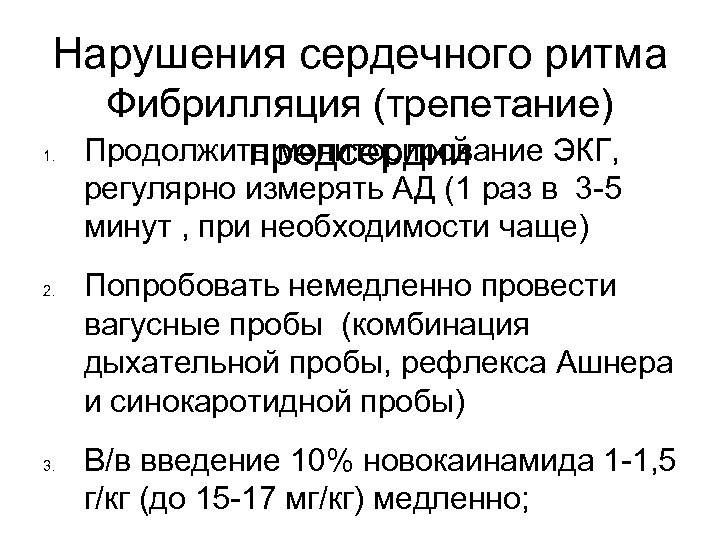

Нарушения сердечного ритма 1. Фибрилляция (трепетание) Продолжить мониторирование ЭКГ, предсердий регулярно измерять АД (1 раз в 3 -5 минут , при необходимости чаще) 2. 3. Попробовать немедленно провести вагусные пробы (комбинация дыхательной пробы, рефлекса Ашнера и синокаротидной пробы) В/в введение 10% новокаинамида 1 -1, 5 г/кг (до 15 -17 мг/кг) медленно;

Нарушения сердечного ритма 1. Фибрилляция (трепетание) Продолжить мониторирование ЭКГ, предсердий регулярно измерять АД (1 раз в 3 -5 минут , при необходимости чаще) 2. 3. Попробовать немедленно провести вагусные пробы (комбинация дыхательной пробы, рефлекса Ашнера и синокаротидной пробы) В/в введение 10% новокаинамида 1 -1, 5 г/кг (до 15 -17 мг/кг) медленно;